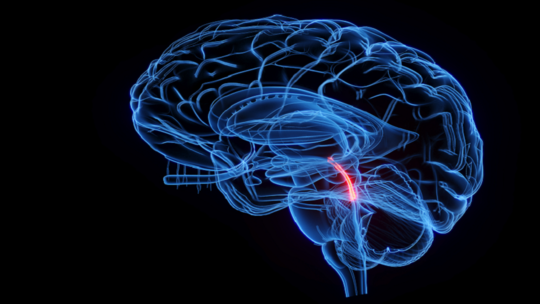

يتكون السائل من الماء والبروتينات والسكر والأيونات والناقلات العصبية، وتنتجه شبكة من الخلايا تسمى الضفيرة المشيمية، والتي تقع في بطينات الدماغ أو تجاويفها.

وتنتج الضفيرة المشيمية حوالي 500 مليلتر من السائل الدماغي الشوكي يوميا، ولكن يتواجد نحو 150 مليلتر فقط داخل الجهاز العصبي المركزي بسبب الامتصاص والتجديد المستمر في الدماغ.